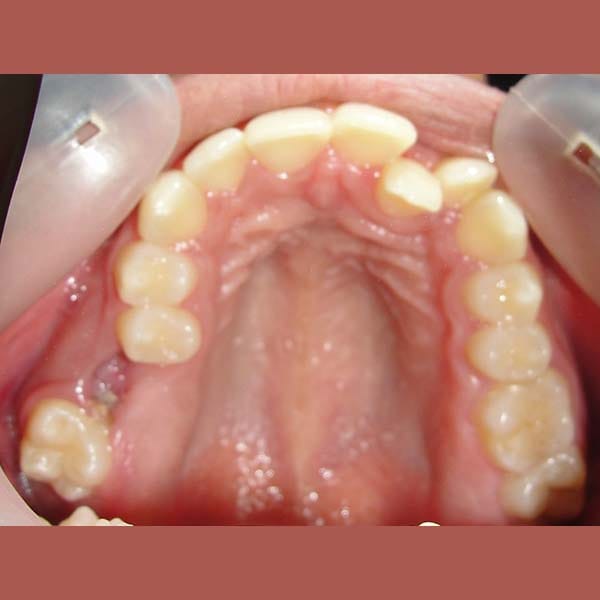

Our young friend suffered from insufficient spaces for her teeth to align properly, which caused her a reverse bite in some of the front teeth.

She also suffered from a severe gummy smile and had a gap resulting from the extraction of an upper molar.

And because she didn’t want to use dental implants, we had to close the gap by moving the molars located behind it forward. This made the situation more difficult and complicated